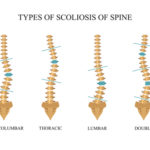

Unsere Zentren für Skoliosetherapie in Leipzig und Markkleeberg bieten Ihnen spezialisierte Behandlungsansätze zur Verbesserung und Stabilisierung Ihrer Wirbelsäulengesundheit. Mit dem bewährten Konzept der dreidimensionalen Schroth-Therapie nach Katharina Schroth setzen wir auf eine effektive und individuell angepasste Therapieform.

Vertrauen Sie auf unsere Expertise in der Behandlung der skoliotischen Wirbelsäulenverkrümmung. Ihr Weg zu mehr Lebensqualität – Skoliosetherapie nach Schroth.